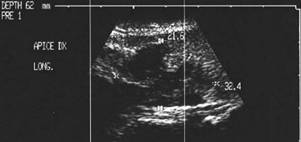

Apexul lobului drept, proiectie longitudinala si trasversala.

Femeie 58 ani. Maladia Graves in tratament cu

metimazol.

Nodul unic in apexul lobului drept, de 11x14x20mm (1,5 cc), hipoecogen, cu

contur difuz

Nu s-a efetuat citoaspiratie.